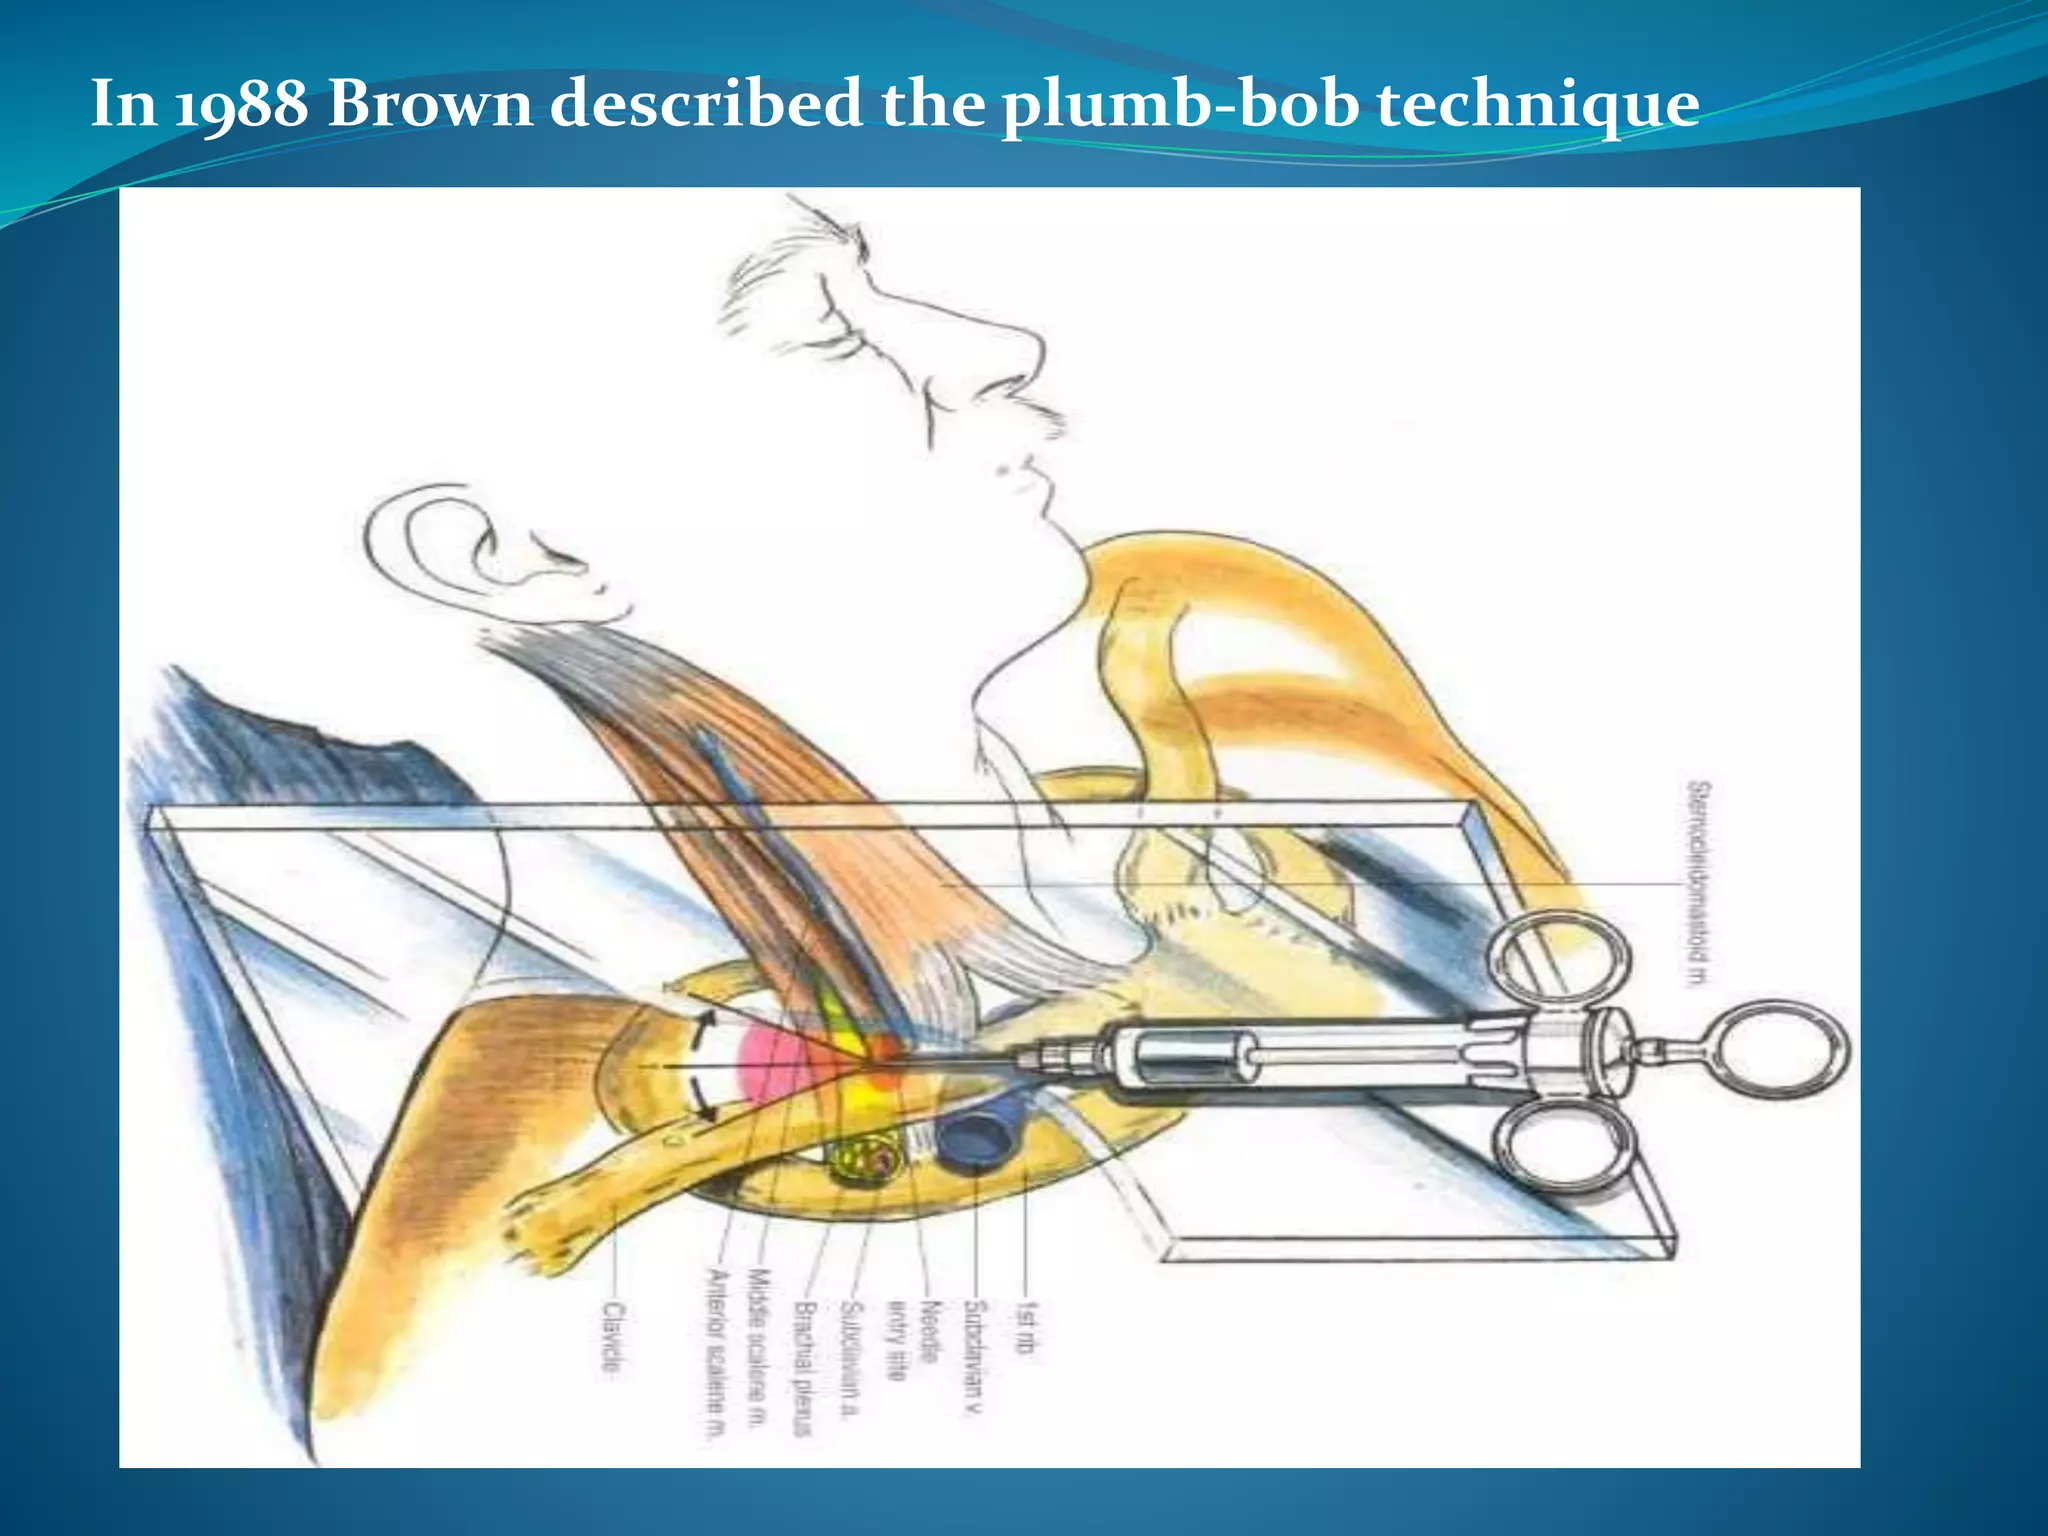

This document provides an overview of brachial plexus anatomy and techniques for brachial plexus nerve blocks. It begins with a description of the brachial plexus formation from cervical and thoracic nerve roots and its branching pattern. Four main approaches for brachial plexus nerve blocks are described: interscalene, supraclavicular, infraclavicular, and axillary. Details are provided on the anatomy and techniques for performing interscalene and supraclavicular brachial plexus blocks. Ultrasound guidance is discussed as an advancement which allows real-time visualization of needle and nerve. Complications are also summarized.